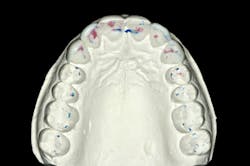

We always complete treatment on our models before we ever begin treatment on our patients, so that we are confident we can achieve the same result in the mouth. Below you will see that we completed a minimal wax-up to recontour the gingival levels and correct proportions and contours. We also worked out Dawson’s 5 requirements of occlusal stability by utilizing equilibration and refining the anterior guidance with our proposed restorations.

These models (figures 7–10) can then be sent to the laboratory for fabrication of the final wax-up, reduction guides, and provisional matrices. In contrast, we could also scan these models and upload the files to perfect our digital wax-up.